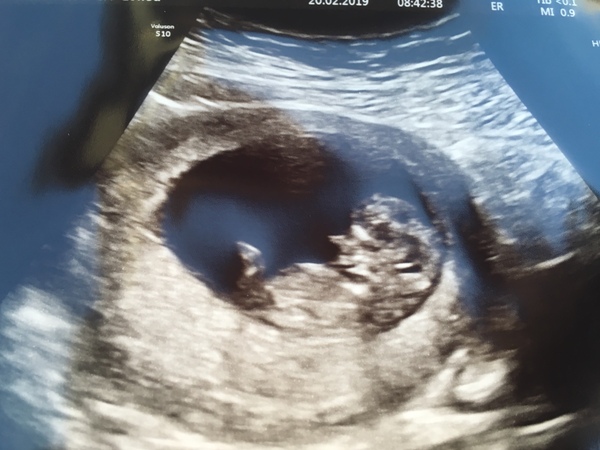

Megan2018 · 20/02/2019 09:17

Scan done, all looks ok, very wriggly. Measuring 10+2 (my dates 10+3). I sobbed. Anxious wait now for results